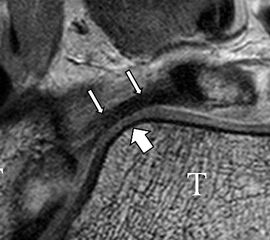

Das Ligamentum tibiofibulare posterius (hintere Syndesmose) verläuft flacher und geht nach kranial in das Ligamentum tibiofibulare interosseus und nach kaudal in das Ligamentum intermalleolare posterius über. Letzteres bildet ein artikuläres Labrum zwischen Trochlea und Talus 9.

Da also die hintere Syndesmose an der posterioren Tibia inseriert, entspricht eine Fraktur oder Infraktion des hinteren Volkmann`schen Dreiecks funktionell einem knöchernen Ausriss des Ligamentum tibiofibulare posterius (Abb. 18 a und b). Aufgrund der Koinzidenz von Syndesmosenläsionen mit Innenbandverletzungen ist bei der Beurteilung gesondert auf solche zu achten.

b. T2 fs axial. Infraktion des hinteren Volkmann‘schen Dreiecks (schmale, weiße Pfeile). Hier inserierende, intakte, hintere Syndesmose (breite, weiße Pfeile).